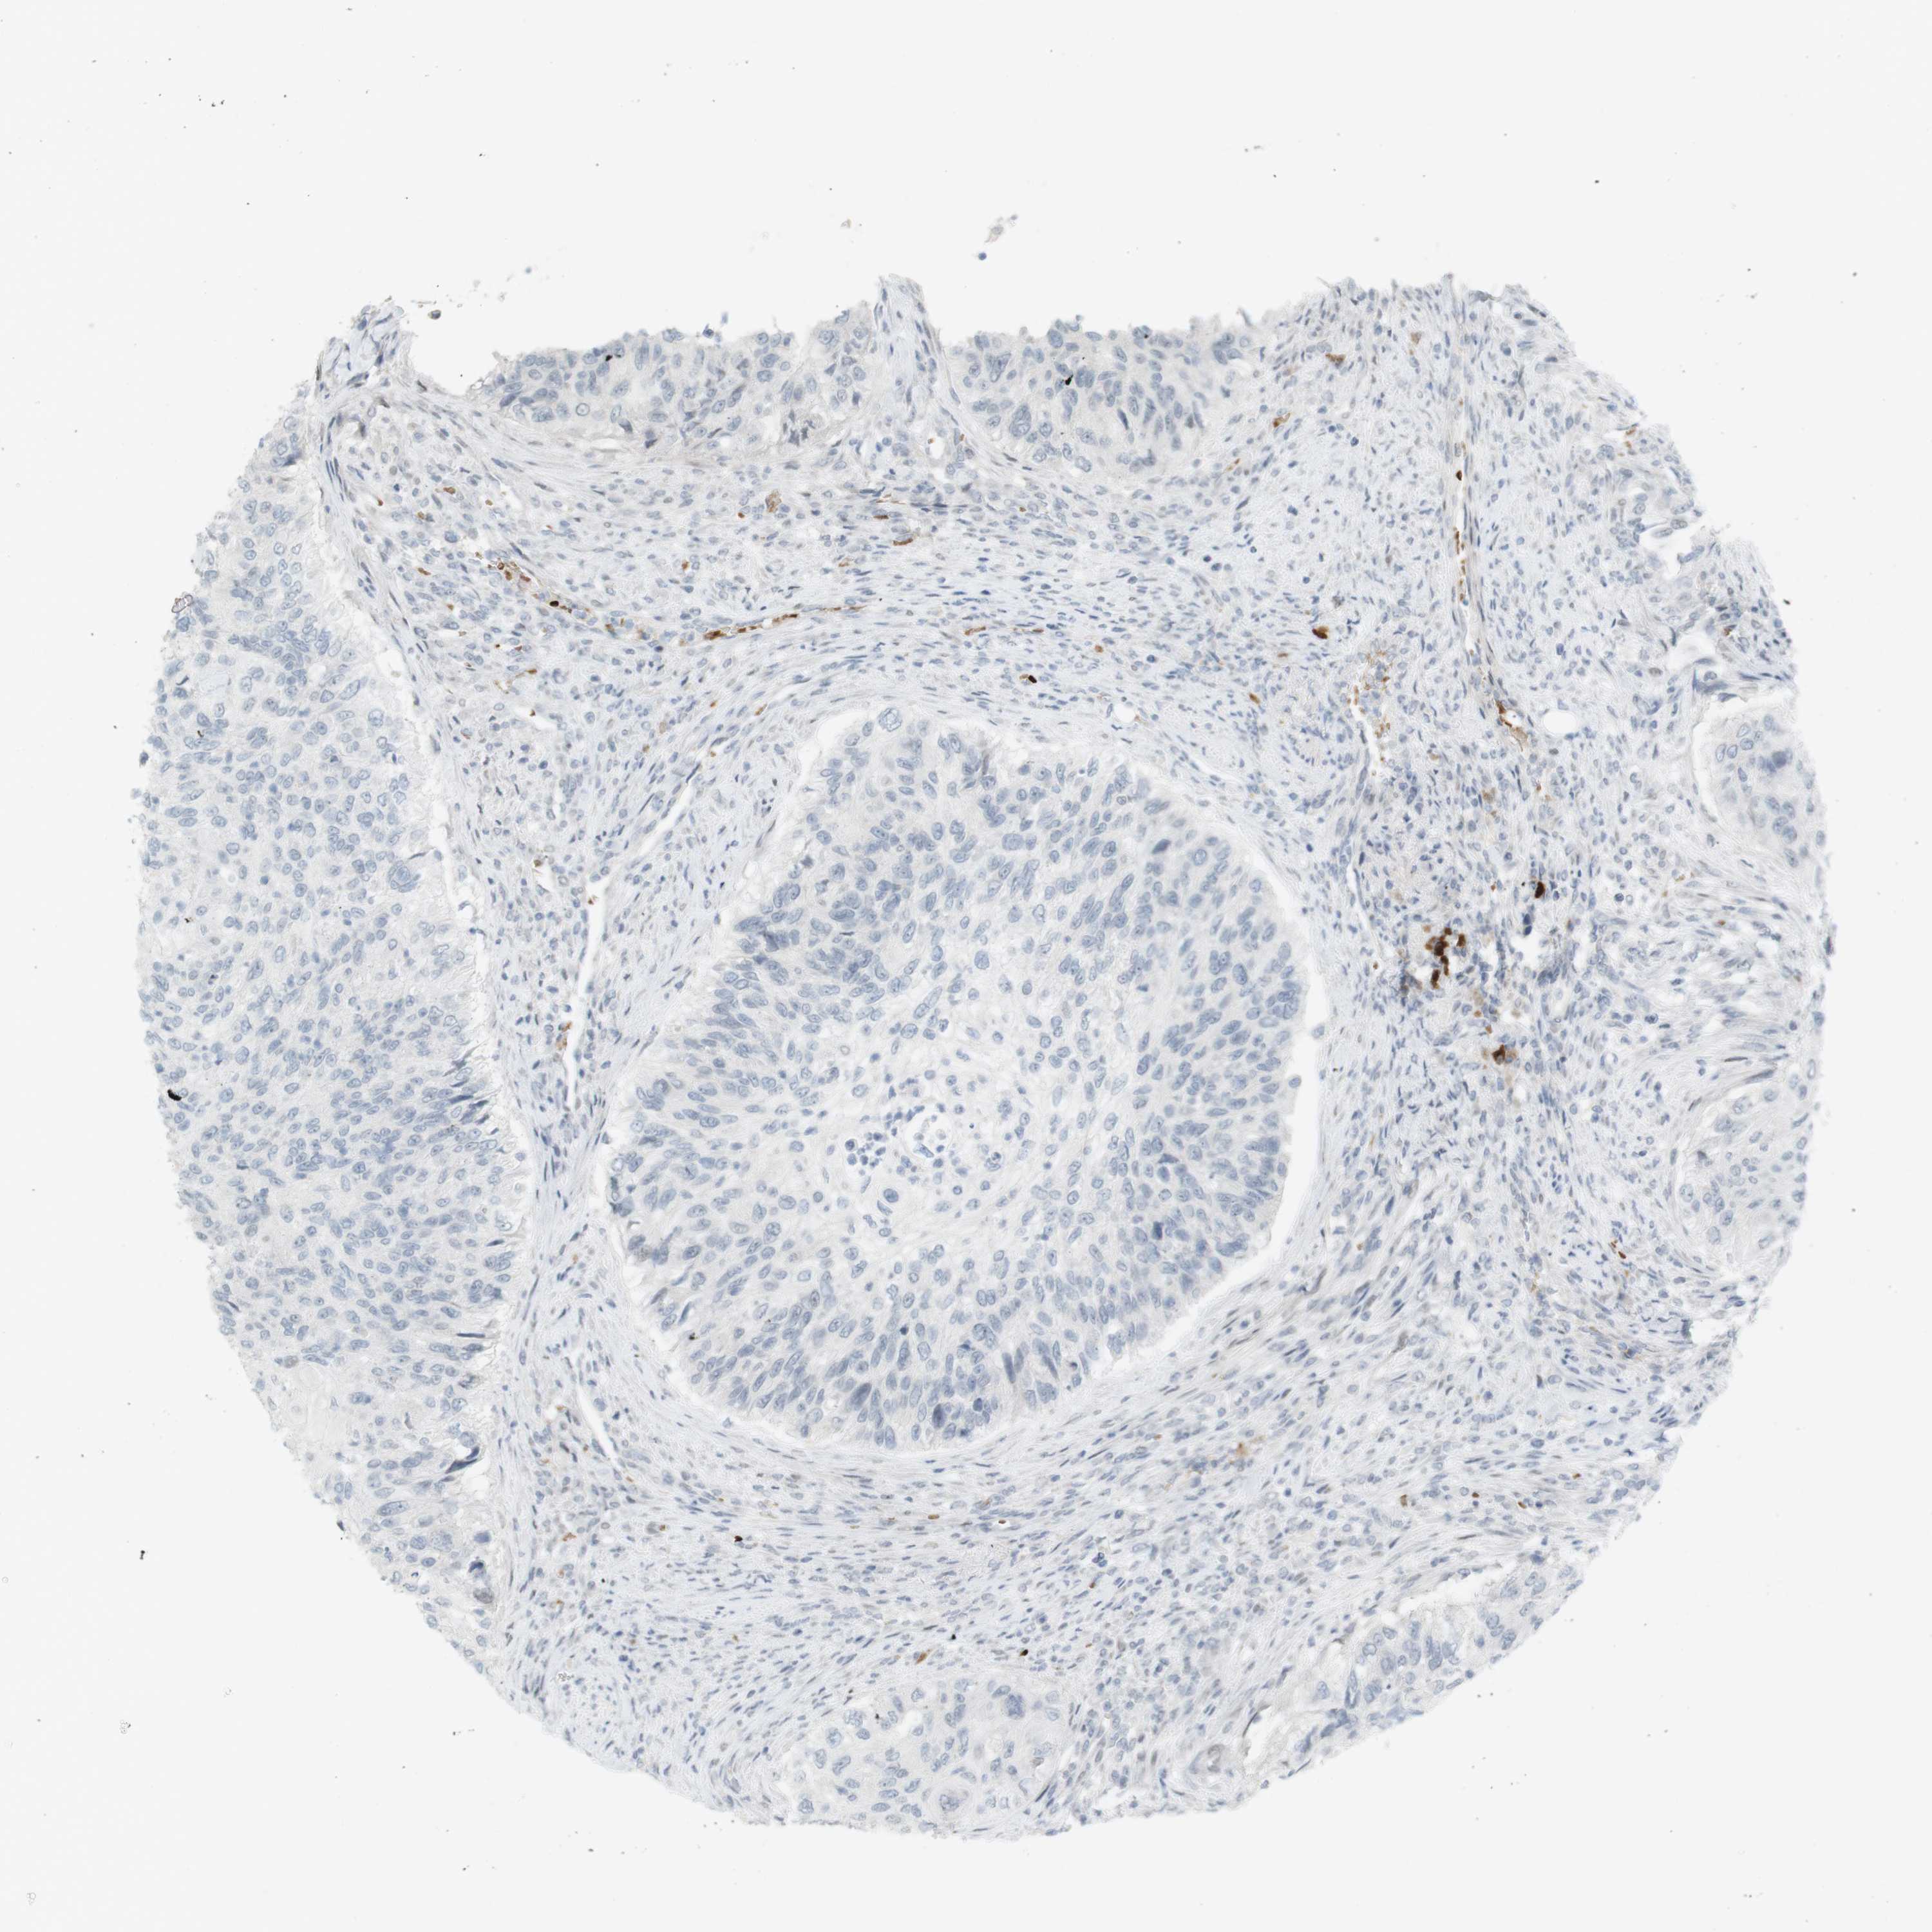

UROTHELIAL CANCER - Protein expressioni

A mouse-over function shows sample information and annotation data. Click on an image to view it in a full screen mode. Samples can be filtered based on level of antibody staining by selecting one or several of the following categories: high, medium, low and not detected. The assay and annotation is described here.

Note that samples used for immunohistochemistry by the Human Protein Atlas do not correspond to samples in the TCGA dataset.

Antibody stainingi

Antibody staining in the annotated cell types in the current human tissue is reported as not detected, low, medium, or high, based on conventional immunohistochemistry profiling in selected tissues. This score is based on the combination of the staining intensity and fraction of stained cells.

Each image is clickable and will lead to virtual microscopy that enables deeper exploration of all samples and also displays staining intensity scores, fraction scores and subcellular localization as well as patient and tissue information for each sample.

Antibody HPA001232

Antibody CAB015397

Staining

High

Medium

Low

Not detected

Intensity

Strong

Moderate

Weak

Negative

Quantity

>75%

75%-25%

<25%

None

Location

Nuclear

Cytoplasmic/membranous

Cytoplasmic/membranous,nuclear

Urothelial carcinoma, High grade

Urothelial carcinoma, Low grade

Adenocarcinoma, NOS